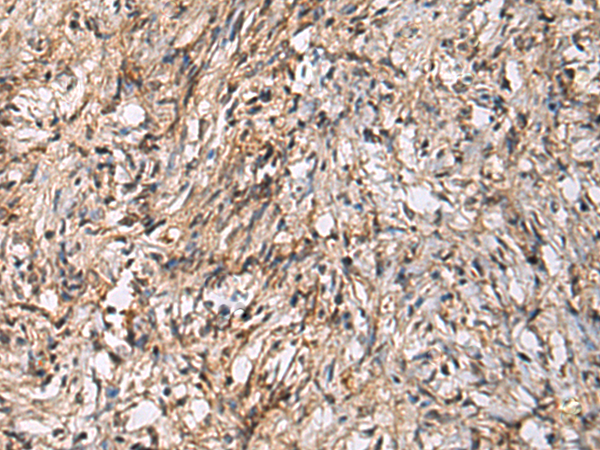

分类: 科研抗体货号: P11831别名: AME; AME1; HSD2; HSD11K; SDR9C3应用: WB,IHC反应种属: Human